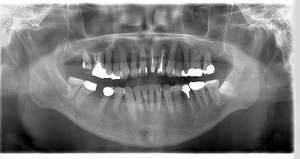

レントゲン写真

- 透過像

| 年齢 | 50代・男性 |

|---|---|

| 主訴 | 右下歯が疼く |

| 治療内容 | ・右下6番インプラント ※1:FGG(遊離歯肉移植術)とは、足りない歯ぐきを上顎から上皮を切り取り移植する外科手術 |

| 治療費 | 合計:902,000円(税込) ■内訳 |

| 治療期間 | 9ヵ月 |

| 治療方針 | 右下の当該歯は歯根破折により保存不可能と診断しました。歯周疾患も伴っていたため抜歯後に骨吸収※1が大きく起こることが予測できました。チタンメッシュ併用骨再生誘導法(GBR※2)を選択しインプラント埋入と同時に行い自然な歯槽骨のラインを再現しました。またGBRを行う際にインプラント辺縁の付着歯肉の減少が起こる為、遊離歯肉移植術(FGG※3)を行い清掃性を考慮した形態に仕上げました。 ■治療方針の解説 治療した右下の歯をレントゲンで撮影したところ根本の部分に黒く写る箇所があり「根尖性慢性周囲炎※1」と診断。また歯周病も進行していました。 ※1 骨吸収・・・歯槽骨という歯を支える骨がなくなっていくこと |

| 担当者所見 | 主訴の右下だけでなく歯茎の腫れ、発赤があり不良補綴や不良充填など他にも治療箇所が多数ありました。プラークコントロールが不良であった為まずはブラッシング指導を行いセルフケアの重要性を理解していただくところからスタートしました。 右下6番の歯はインプラント治療を行なった結果審美的にも機能的にも患者様の満足を得ることができました。骨造成と歯肉移植も行なった為インプラントを支える十分な歯周組織の獲得ができたと思っております。 |